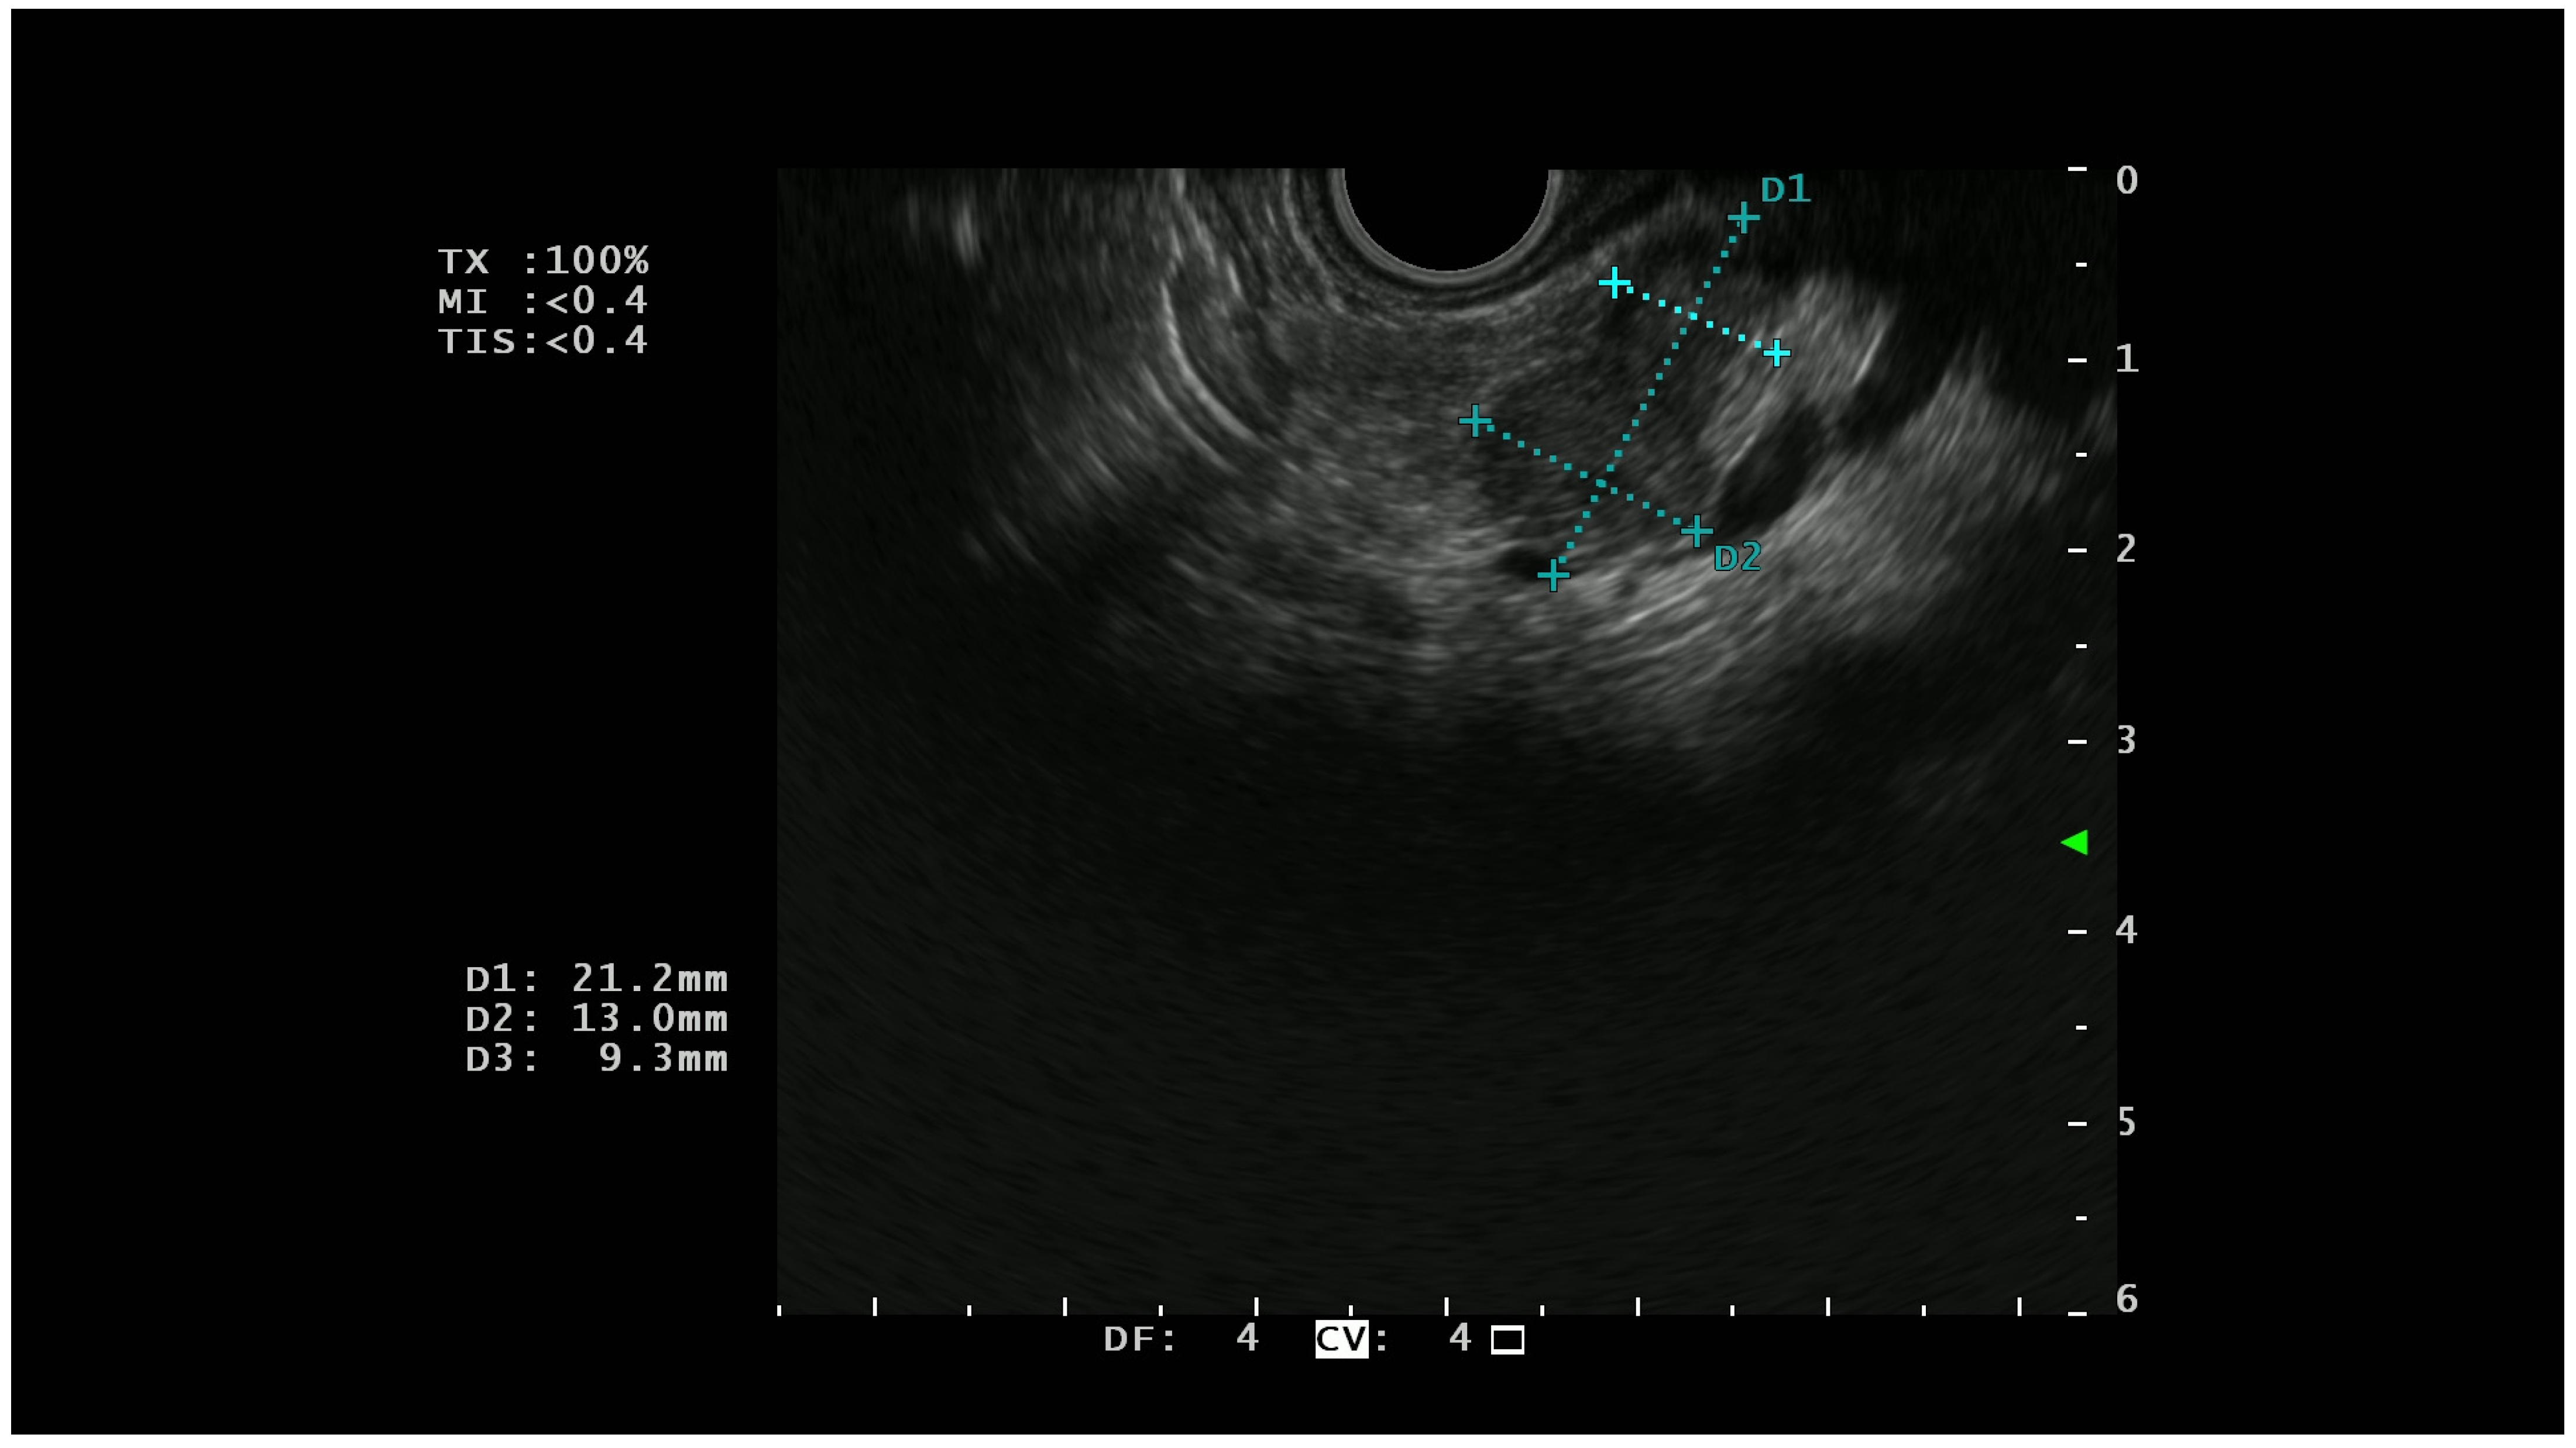

On EUS, basal analysis PTENs typically appear as homogeneous hypoechoic lesions with regular margins (Figure 1); sometimes they can have a cystic appearance [22] while in the most advanced cases, they can lose these characteristics, acquiring features more similar to pancreatic adenocarcinoma [23].

Figure 1.

A hypoechoic lesion of 21 mm with regular margins (identified by the blu +) and an ipoechoic appearance; at histopathological analysis the lesion was a G1 NET.